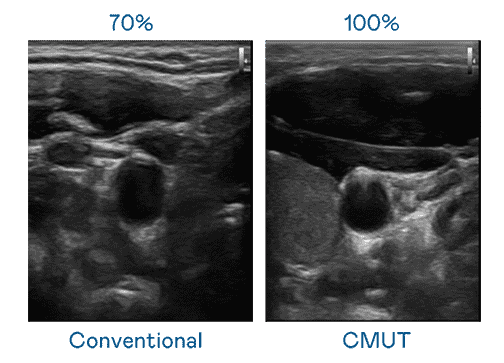

CMUT 技术是一种用电容式微机电元件来产生超音波讯号的技术。。。与传统 PZT 压电式技术相比,,,,CMUT 频宽增加 30%,,更宽频的超音波讯号让影像解析度大幅提升,,,是实现高影像品质医疗超音波扫描、、、促进精准医疗发展的关键技术。。。。

大频宽带来超清晰影像

超音波影像的解析度高低,,,,首先取决于探头能发出的讯号频宽。。OBPay CMUT 可提供高清晰的超音波讯号,,提供高频宽、、、高灵敏度、、、影像纹理细节更高的超音波影像,,,,协助医护人员缩短影像判读时间及利用精准的医疗影像进行诊断。。。